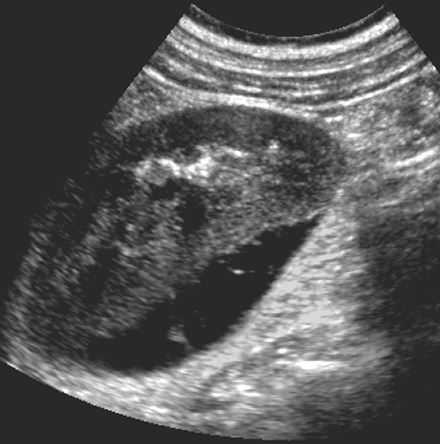

Testicular epidermoid cyst

• benign germ cell neoplasm

• monodermal teratoma - only ectodermal components

• appearance

• well-marginated lesoins that are typically hypoechoic

• hyperechoic rim with complete or partial rim of calcification

• onion ring/peel appearance